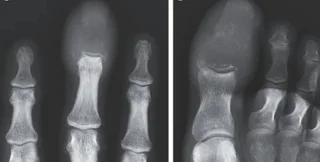

Во время обследования пациента врачи обнаружили, что кончики опухших пальцев были на ощупь плотными и покрасневшими. Дальнейшее сканирование показало, что раковая опухоль полностью заменила кости в пальцах руки и ноги мужчины. Речь идет о литических поражениях – области, где разрушается кость, оставляя отверстия или пустые пространства в скелете. Такие поражения обычно вызваны патологическим процессом, например, раком.

Давно известно, что рак, распространившийся на кости, может имитировать подагру или остеомиелит. Но рентгенография помогает поставить точный диагноз.

На основе рентгенограммы у 55-летнего пациента был диагностирован акрометастаз, который является редкой формой рака, встречающаяся ниже локтя или колена. Акрометастазы составляют лишь около 0,1% случаев распространения рака на кости.